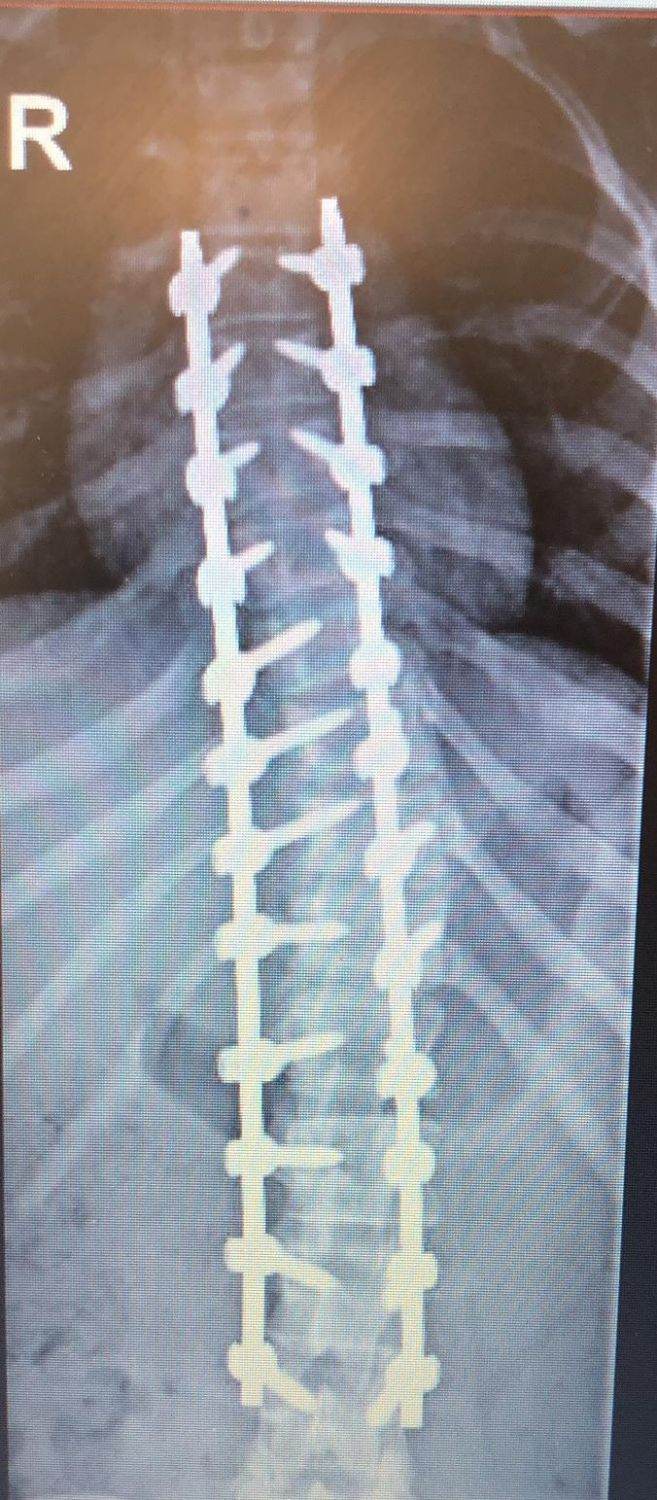

The operation lasted five and a half hours. There were 12 segments from thoracolumbar 5 to L4, and 24 pedicle screws were needed on both sides; the higher the number, the higher the chance of error. Furthermore, Leilani’s scoliosis was serious, and the deformation and rotation of each vertebral body were different, so each screw needed to be adjusted accordingly. Finally, screw rods were placed on both sides to correct the deformity and fix them in place.

Leilani’s X-ray examinations (before & after operation)